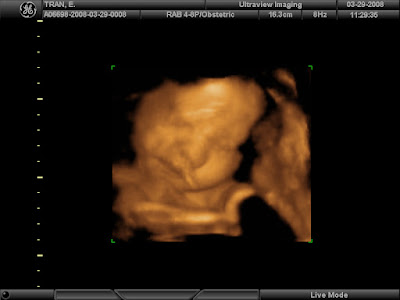

Nice to see you Baby Collin!

Here are some pictures from our 3D/4D sonogram this weekend. It is so amazing that you can actually see Collin's face. I think he has daddy's nose. He's a LAZY baby....we saw him yawn 3 times during the sonogram despite mommy's breakfast of an cream filled eclair and a soda. That didn't even kick start him.

Here's some face shots....check out his nose! Unfortunately, with the way he was positioned, the umbilical cord was in the way and not enough amniotic fluid was around his face to get a clear picture.

Here he has his hand up against his face.

YAAAAAAAAAAAAAAWN. It's a hard job being all cramped in there.